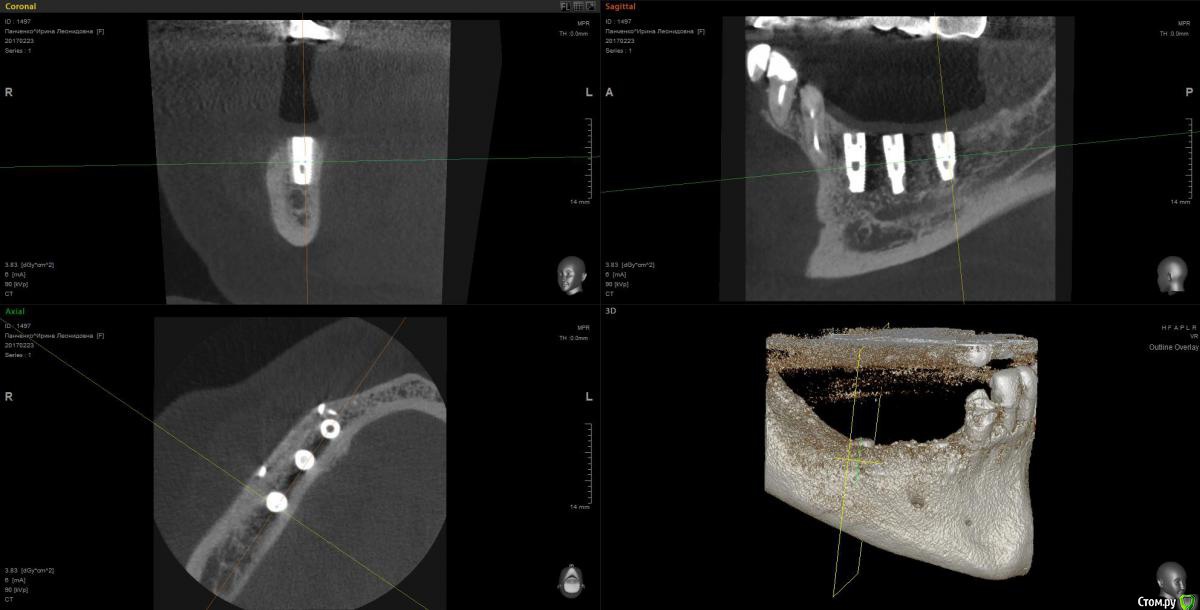

Kostoprav Опубликовано 13 марта, 2017 Поделиться Опубликовано 13 марта, 2017 рецепт сосиски: 70%биопласт by владмива +30%аутокость, мембрана hyprosorb кт до кт сразу после имплантации кт через пол года 3 Ссылка на комментарий

Kostoprav Опубликовано 14 марта, 2017 Автор Поделиться Опубликовано 14 марта, 2017 по порядку 8 Ссылка на комментарий